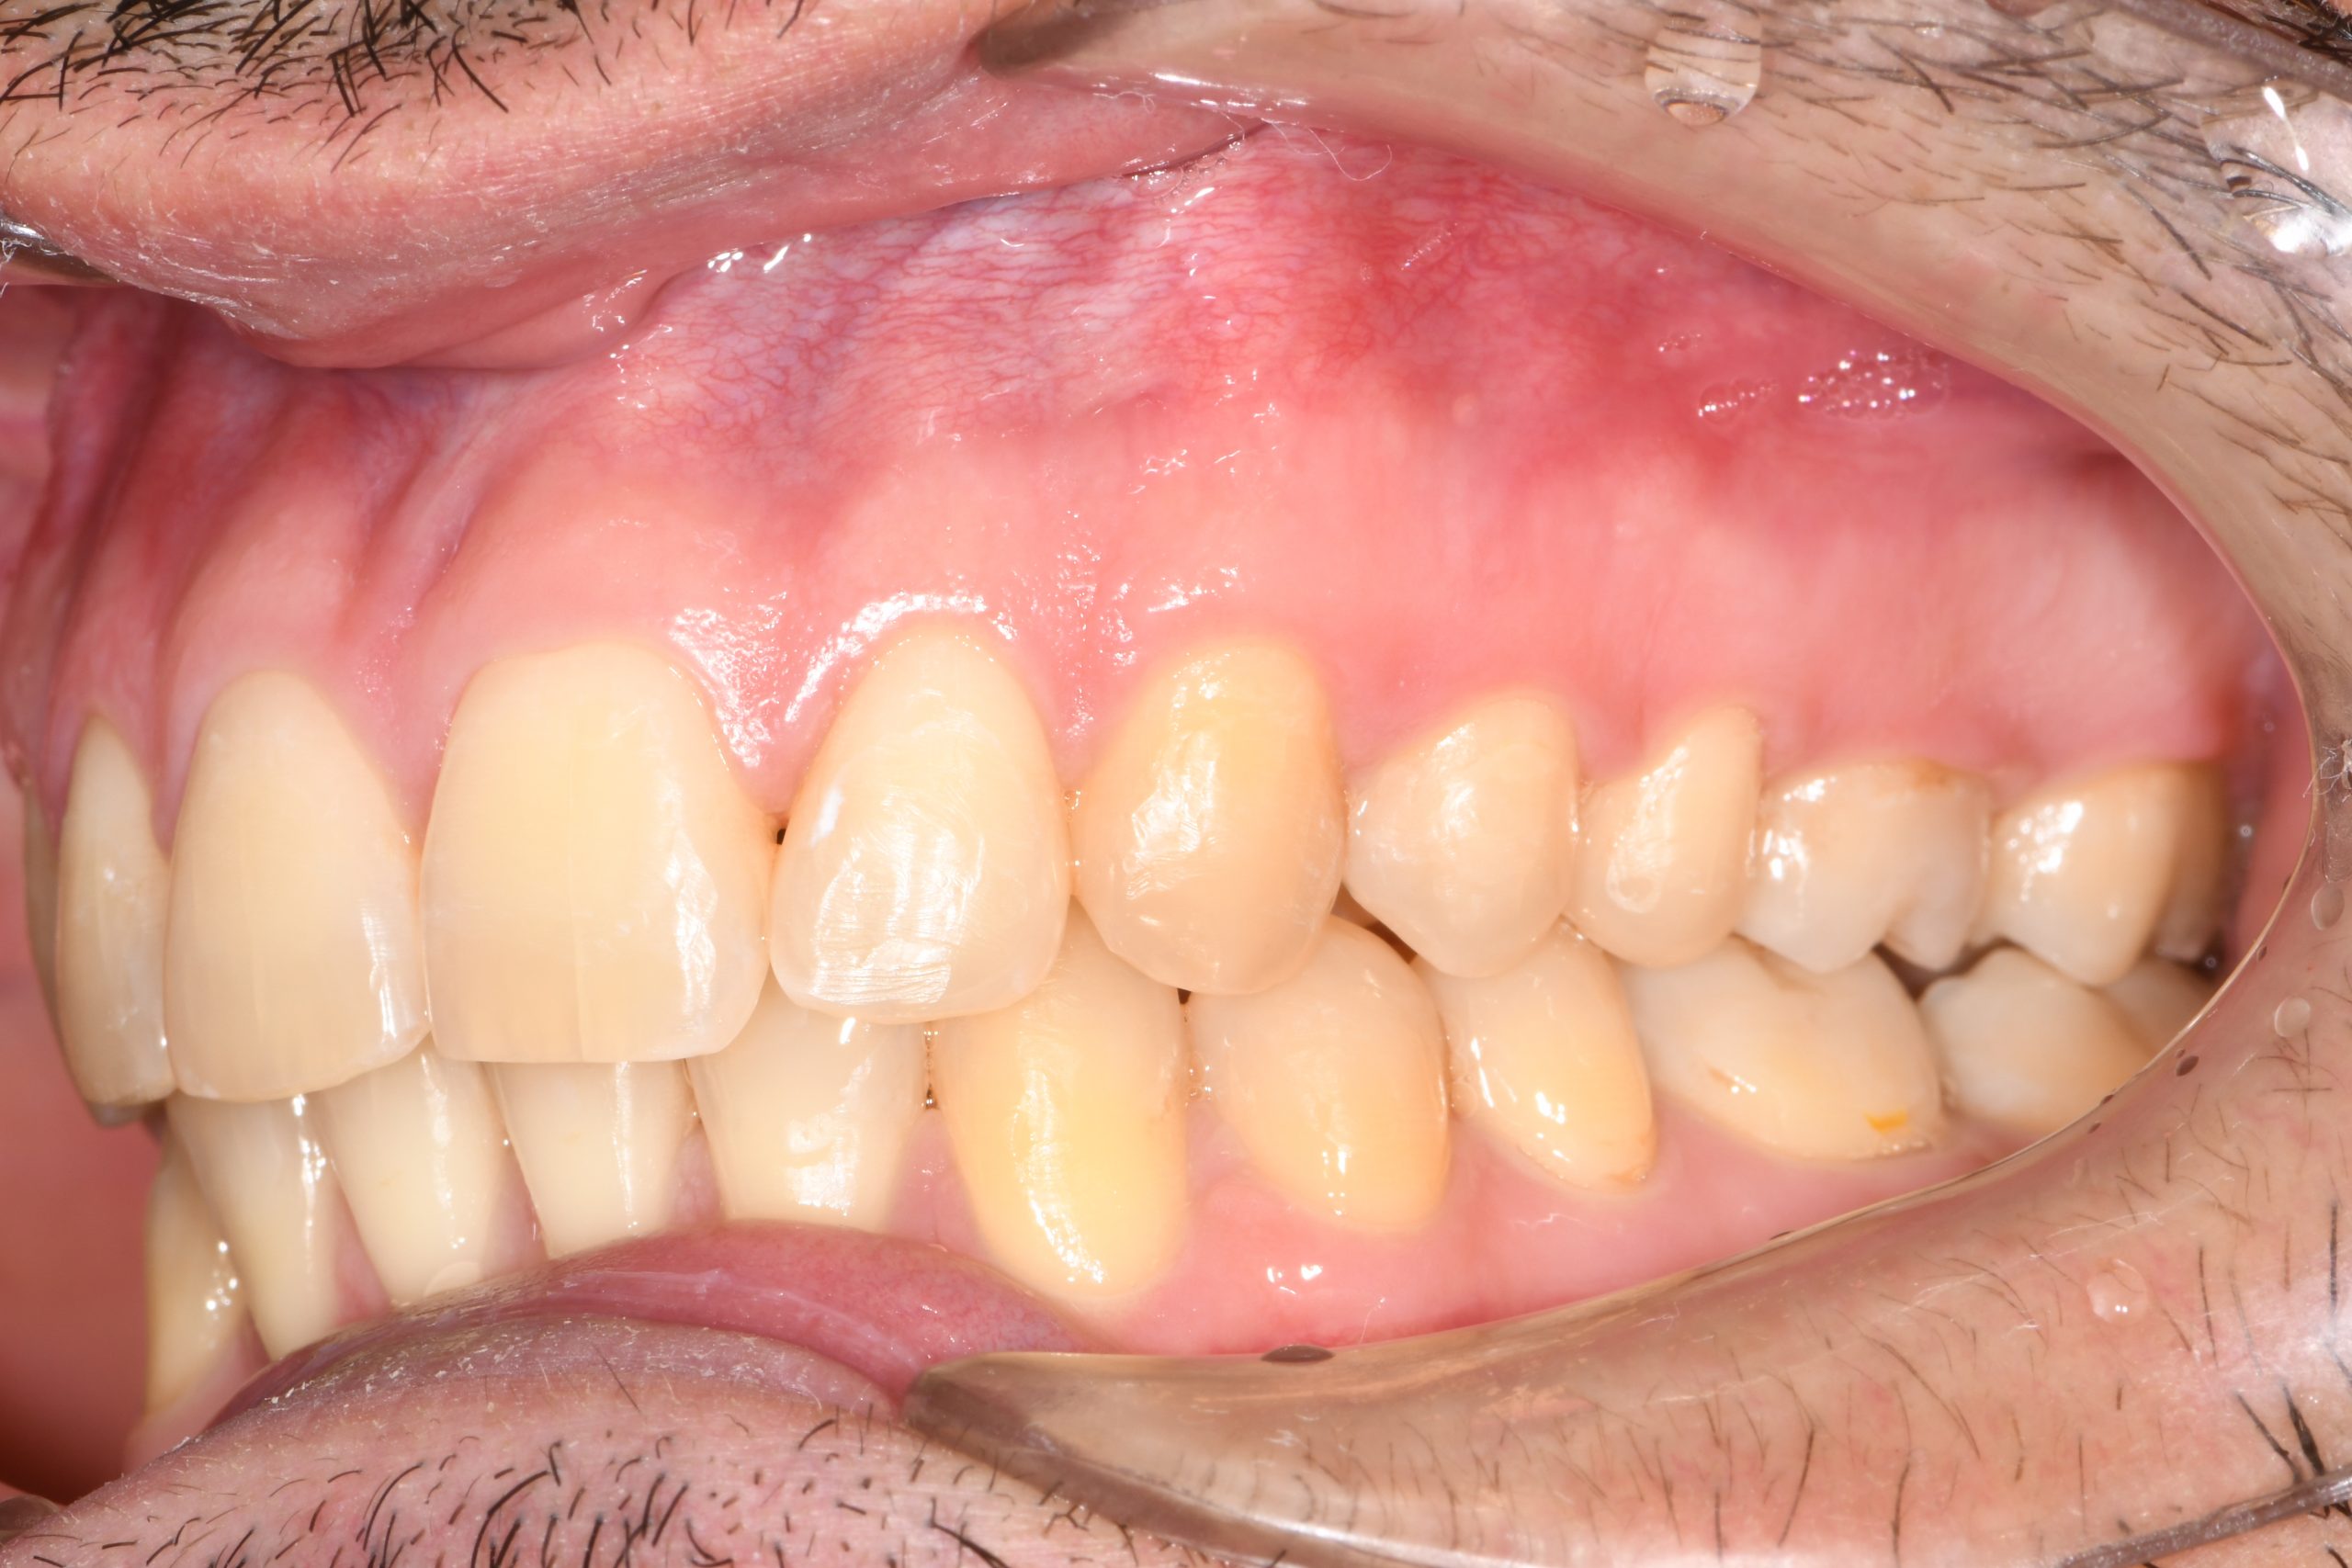

Az elmúlt évekből rengeteg szakmai referenciát tudnánk bemutatni, amelyek különböző fogszabályozási problémákat oldottak meg. Válogatva a több száz esetből, ezen az oldalon olyan képeket, információkat igyekeztünk bemutatni, amelyeknek a segítségével a jövőbeni pácienseinknek azt tudjuk üzenni: A Te fogsorod is lehet gyönyörű!